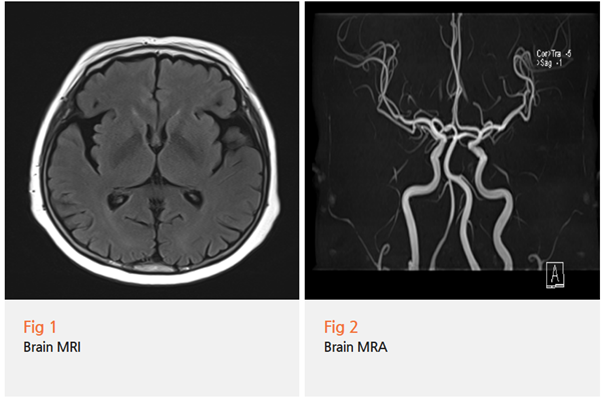

뇌 MRI와 MRA를 통해

뇌경색이나 다른 구조적 문제는 없는 것을 확인했고

신경학적 검사와 임상 증상을 종합한 결과...

파킨슨병 진단을 내렸습니다.